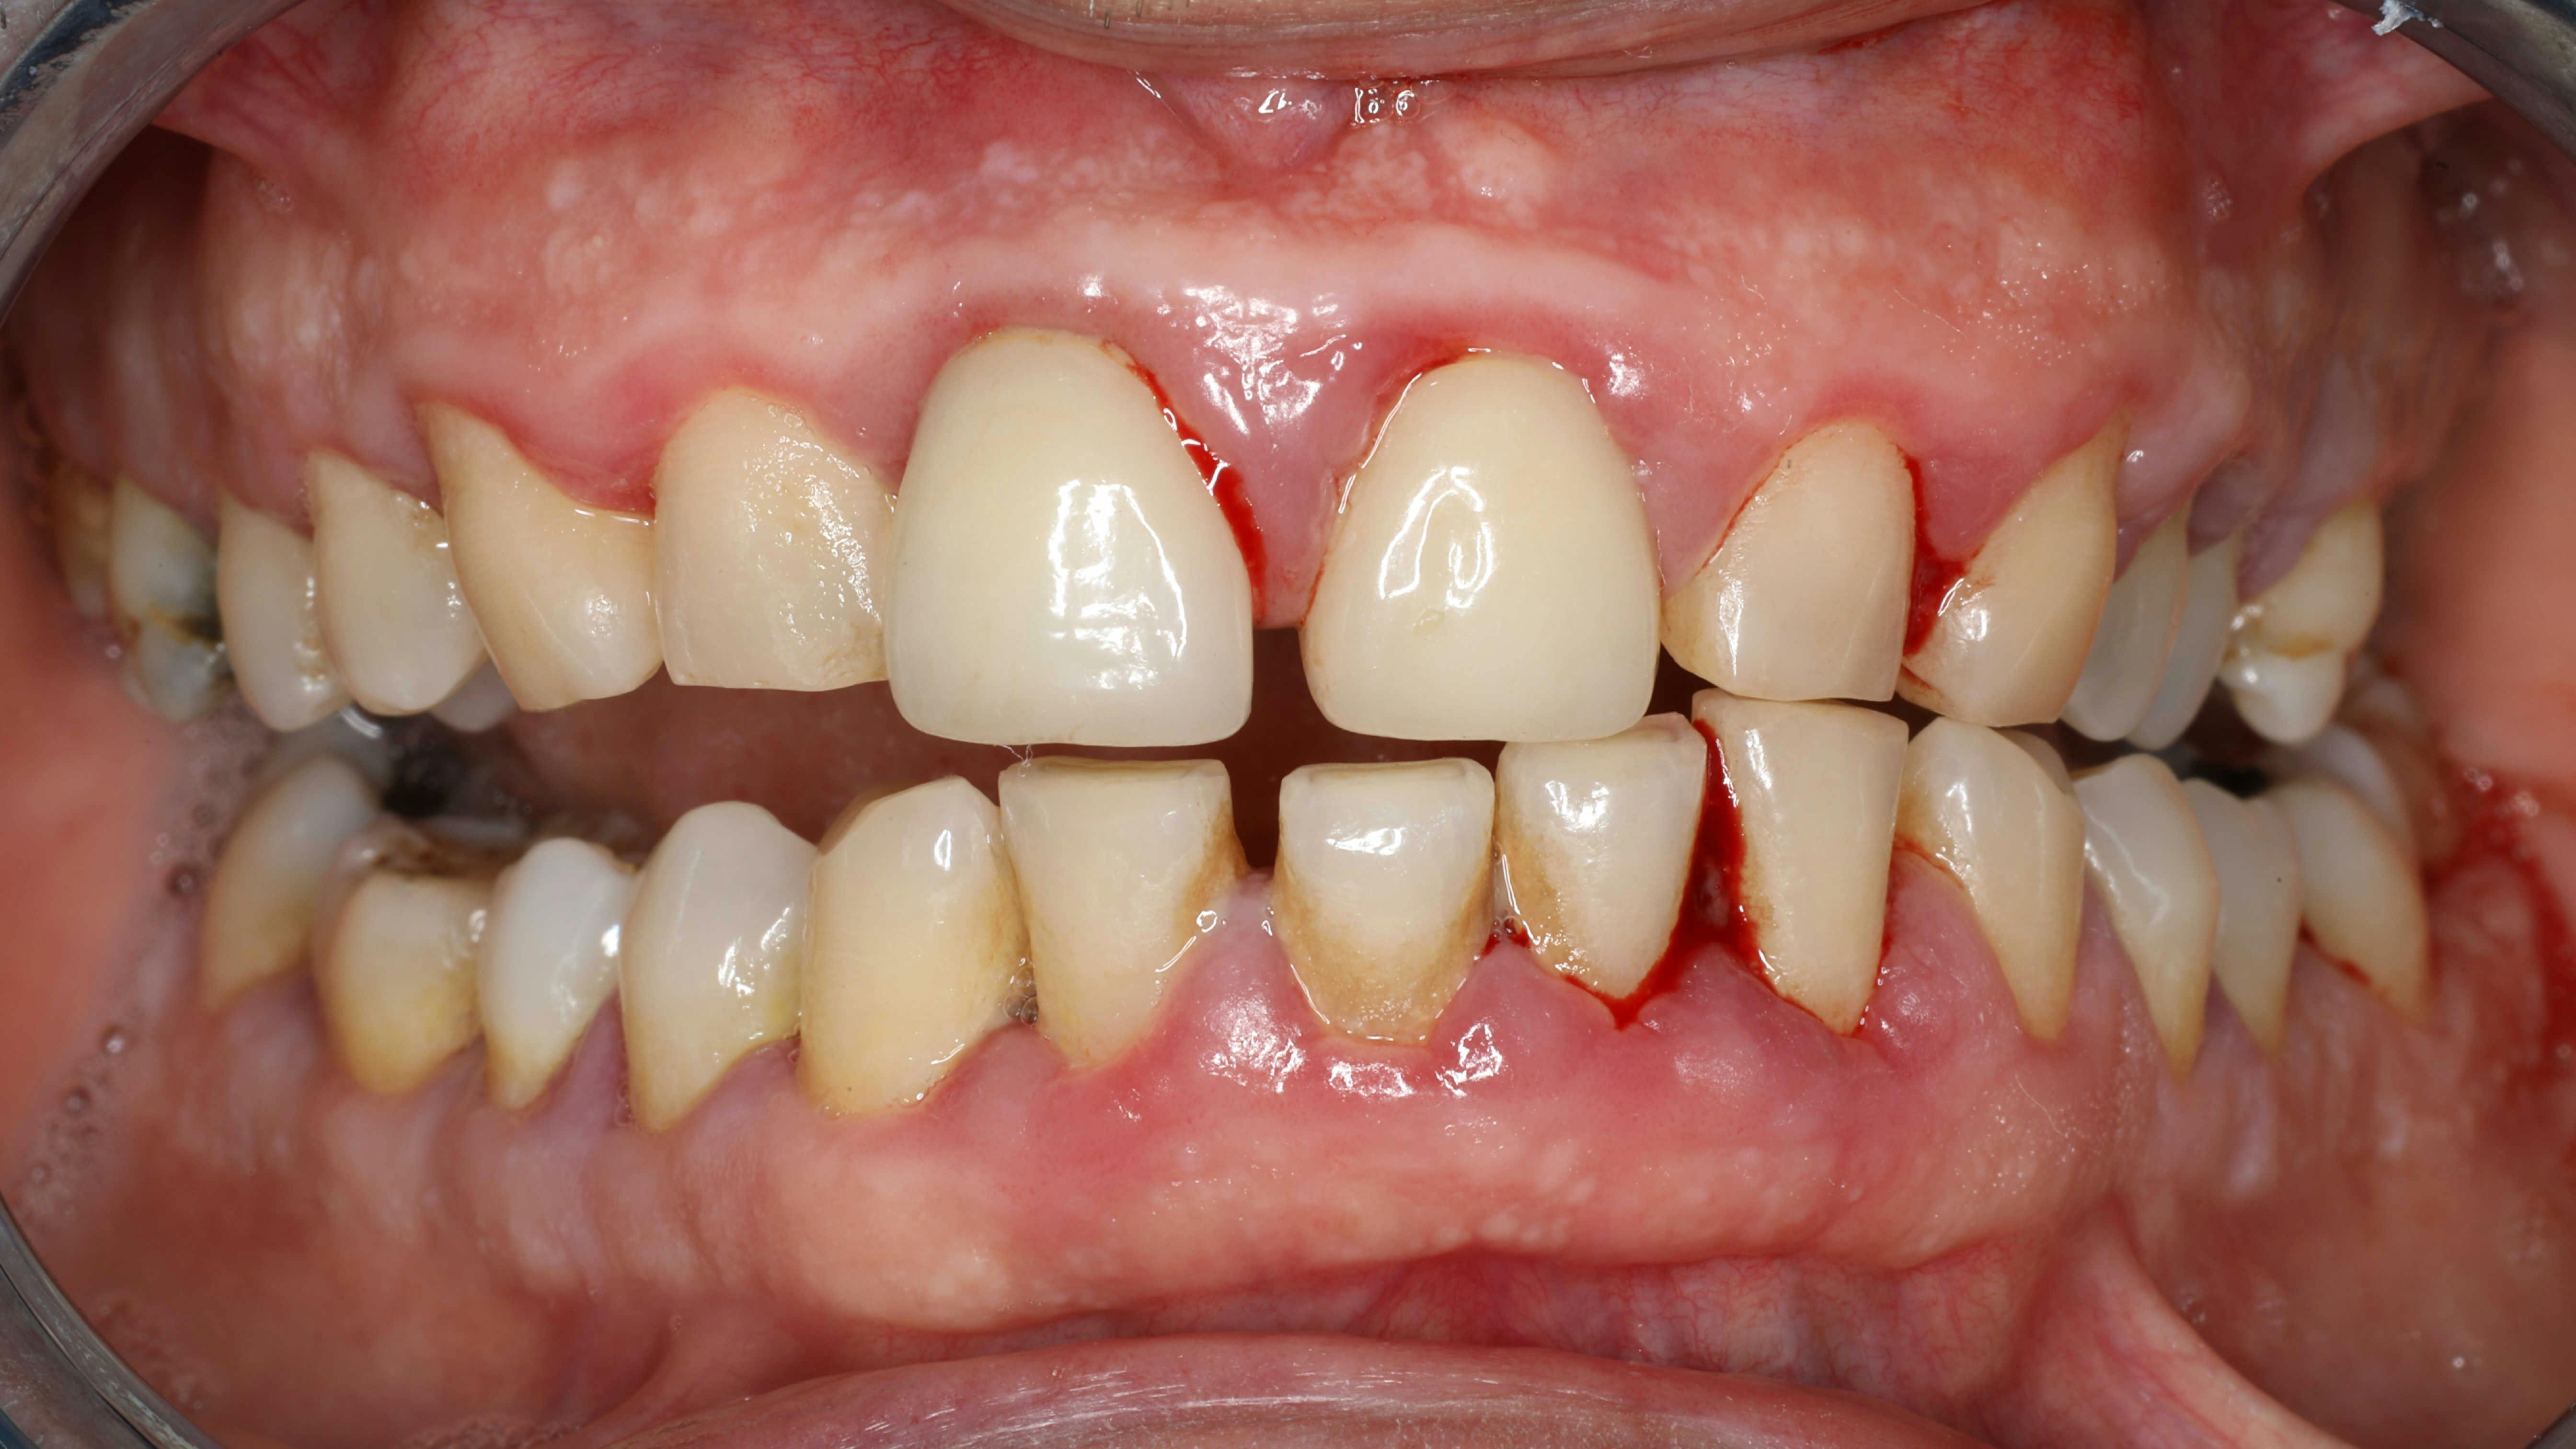

clinical photo of periodontal disease

Evidence increasingly links chronic periodontitis to Alzheimer’s disease through oral dysbiosis and inflammation. Periodontal pathogens like Porphyromonas gingivalis may contribute...

Jan. 5, 2026

Liudmila Chernetska/iStock/Getty Images Plus